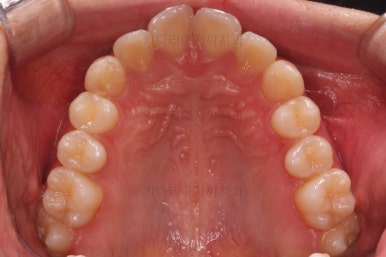

초진 시의 다른 부위들 사진입니다.

약간의 주걱턱 느낌에 약간의 돌출감, 전반적인 치열의 가지런한 느낌은 나쁘진 않았지만 약간의 불량한 교합상태였어요.

전후사진을 비교해 볼게요.

약간의 주걱턱, 돌출입은 고칠 의사가 없어서 그대로 유지하였고 주걱턱 패턴으로 인한 부정교합 부분을 개선했으며 무엇보다 중요한 것은 쓰러져서 많이 썩어있던 치아를 자칫 치료 못할 뻔 했는데 교정치료와 병행하여 훌륭하게 치료를 하여 살려 썼다는 점입니다.